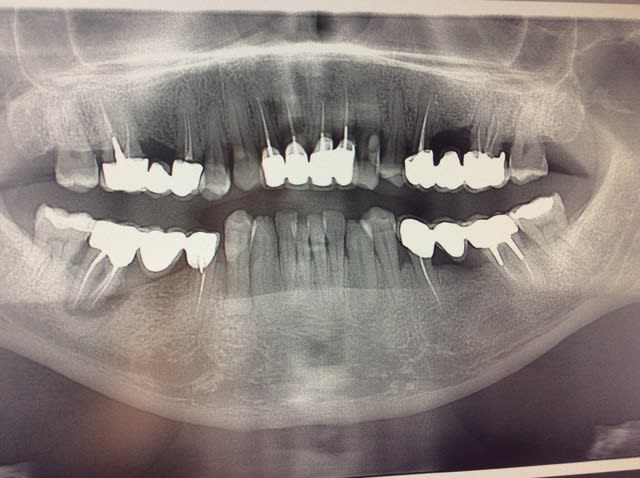

endo ou pas de la 44 avec une racine à la rocco sifredi !!!

Merci pour la radio elle est à produire dans les bêtisiers de Rayons X XXX

Tu ne vas pas nous dire que tu veux refaire le bridge en sect 4?....

lol inversement proportionnel à la taille du screwpost sur la 45

C'est un apex pour le moins coucougnesque...

moi je trouverais un prétexte pour extraire ;-)